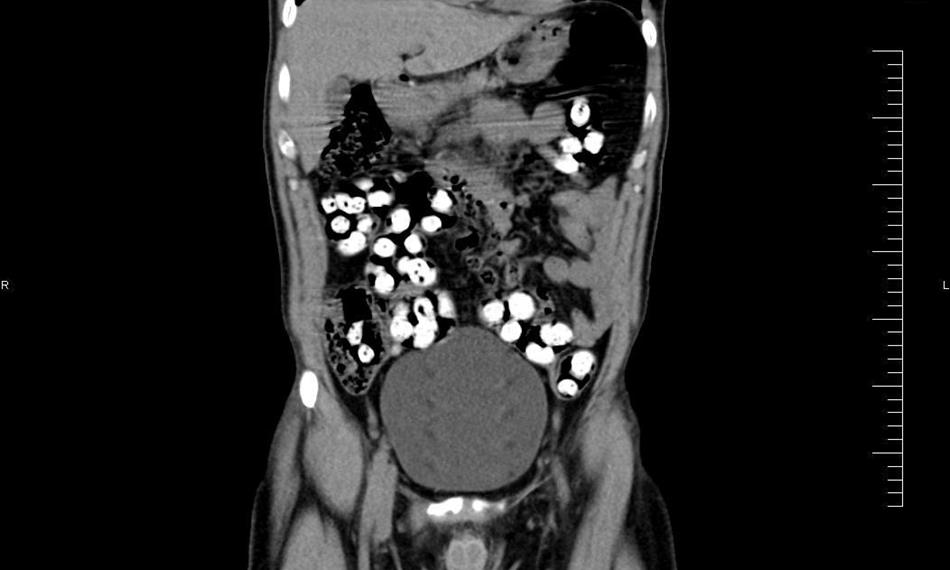

Ke kontrole byl polykač celníky vytipován na základě provedené rizikové analýzy daného letu. Prvotní podezření na pašování drog celníkům potvrdily kontrolní stěry z rukou pašeráka.  Při důkladné kontrole jeho zavazadel a osobní prohlídce nebyly drogy nalezeny, proto bylo provedeno následné rentgenové vyšetření (viz.foto).

Postupně z těla pašeráka vyšlo všech 107 kontejnerků naplněných tuhou hmotou černé barvy. Chemická látka při provedení detekční zkoušky pozitivně reagovala jako opiát. Celková hmotnost všech kapslí včetně drogy je 856 gramů. Určení vlastní hmotnosti a druhu zajištěné drogy je předmětem další odborné expertízy. Podle zkušeností celníků se s největší pravděpodobností jedná o surové opium. Tento druh drogy není na českém trhu obvyklý a zřejmě byla určena k distribuci v jiné zemi.